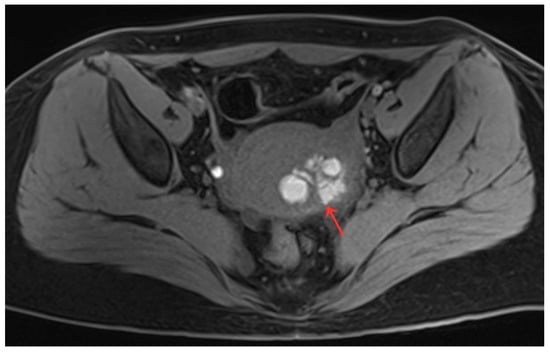

Figure 3.

(a,b) Pelvic MRI shows lesions after HIFU treatment (1st month)(red arrows).